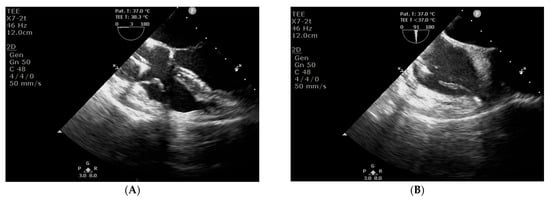

2. Case Presentation